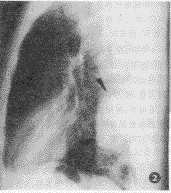

X线检查:正位片示左肺下野一密度中等、均匀,边缘清晰的椭圆形肿块,与左心缘重叠,心缘遮盖征阴性(图1);侧位片示肿块与脊柱重迭,其内未见钙化、空洞等征象(图2)。

图1,2 胸部后前位及左侧位片,左下肺野见椭圆形肿块,心缘遮盖征阴性;侧位片示肿块与脊柱重迭 图3 肿块自后胸壁突向肺叶,边缘清晰,密度均匀,呈水样密度, http://www.100md.com